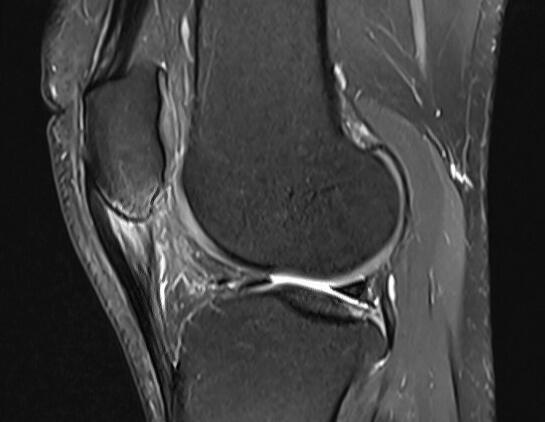

Patellar tendinopathy (MRI scan)

Image gallery

Some examples of our work